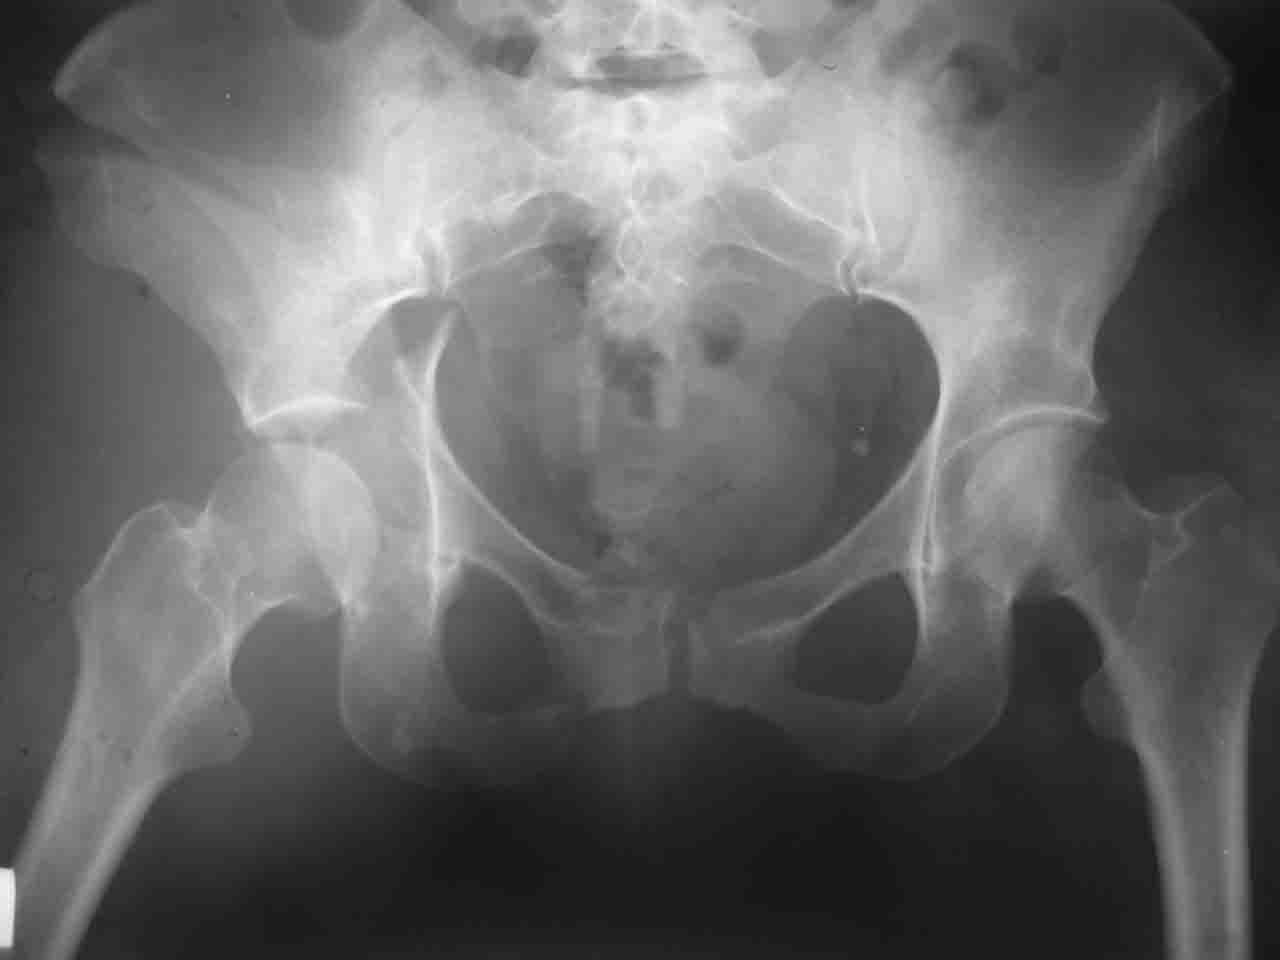

Интерес к реконструкции вертлужной впадины у меня появился довольно-таки давно, но до недавнего времени как-то не ощущалась готовность к практической реализации, а местный подход достаточно консервативен - перелом срастется,

а далее будет видно. Такую точку зрения я не разделяю, поэтому через конференции,ортофорум и свои случаи пытаюсь практически и теоретически *продвинуть* для себя тему реконструкции вертлужной впадины.

> А какой отдел вертлужной впадины более важен - передний или задний?

Однозначного ответа у меня нет : лучше быть богатым и здоровым , чем бедным и больным :-))

Логика подсказывает, что все-таки лучше иметь анатомически полноценную впадину, хотя ранее упоминалось состояние вторичной конгруэнтности и одно наблюдение у меня есть, когда у больного с полностью нарушенной анатомией впадины и подвывихом головки бедра кзади и кверху боли отсутствовали при относительно достаточном для стиля жизни больного объёме движений. Но это только одно наблюдение и кроме перелома впадины у этогобольного была и тяжелая ЧМТ в анамнезе. Основываясь на формулировке структуры ацетабулюм Э. Летурнеля - как перевернутой буквы Y, впадина для полноценной функции сустава должна иметь сферичность, соответствующую размеру головки бедра и если один из компонентов в дефиците, то функциональные последствия рано или поздно проявятся.

> был обусловлен выбор доступа к суставу?

Сложностью, ассоциативностью характера перелома, я бы с радостью воспользовался мининвазивной перкутанной фиксацией винтами, но боюсь, что результат был бы ещё хуже, техникой непрямой репозиции перелома не владею, поэтому пытаясь получить анатомичную впадину приходится широко открывать, по крайней мере пока, а дальше буду пытаться уменьшать пространство...

> передним доступом на двухколонный перелом?

Илеофеморальный доступ не совсем передний и сравнительно с илеоингвинальным, и Кохера-Лангенбека открывает весь наружный таз кроме самых передних отделов лонных костей, фиксацию которых я не ставил в задачу. Обширность диссекции, большая длительность операции и более высокий риск гетерооссификации - отрицательные моменты в обмен на возможность легче ориентироваться.